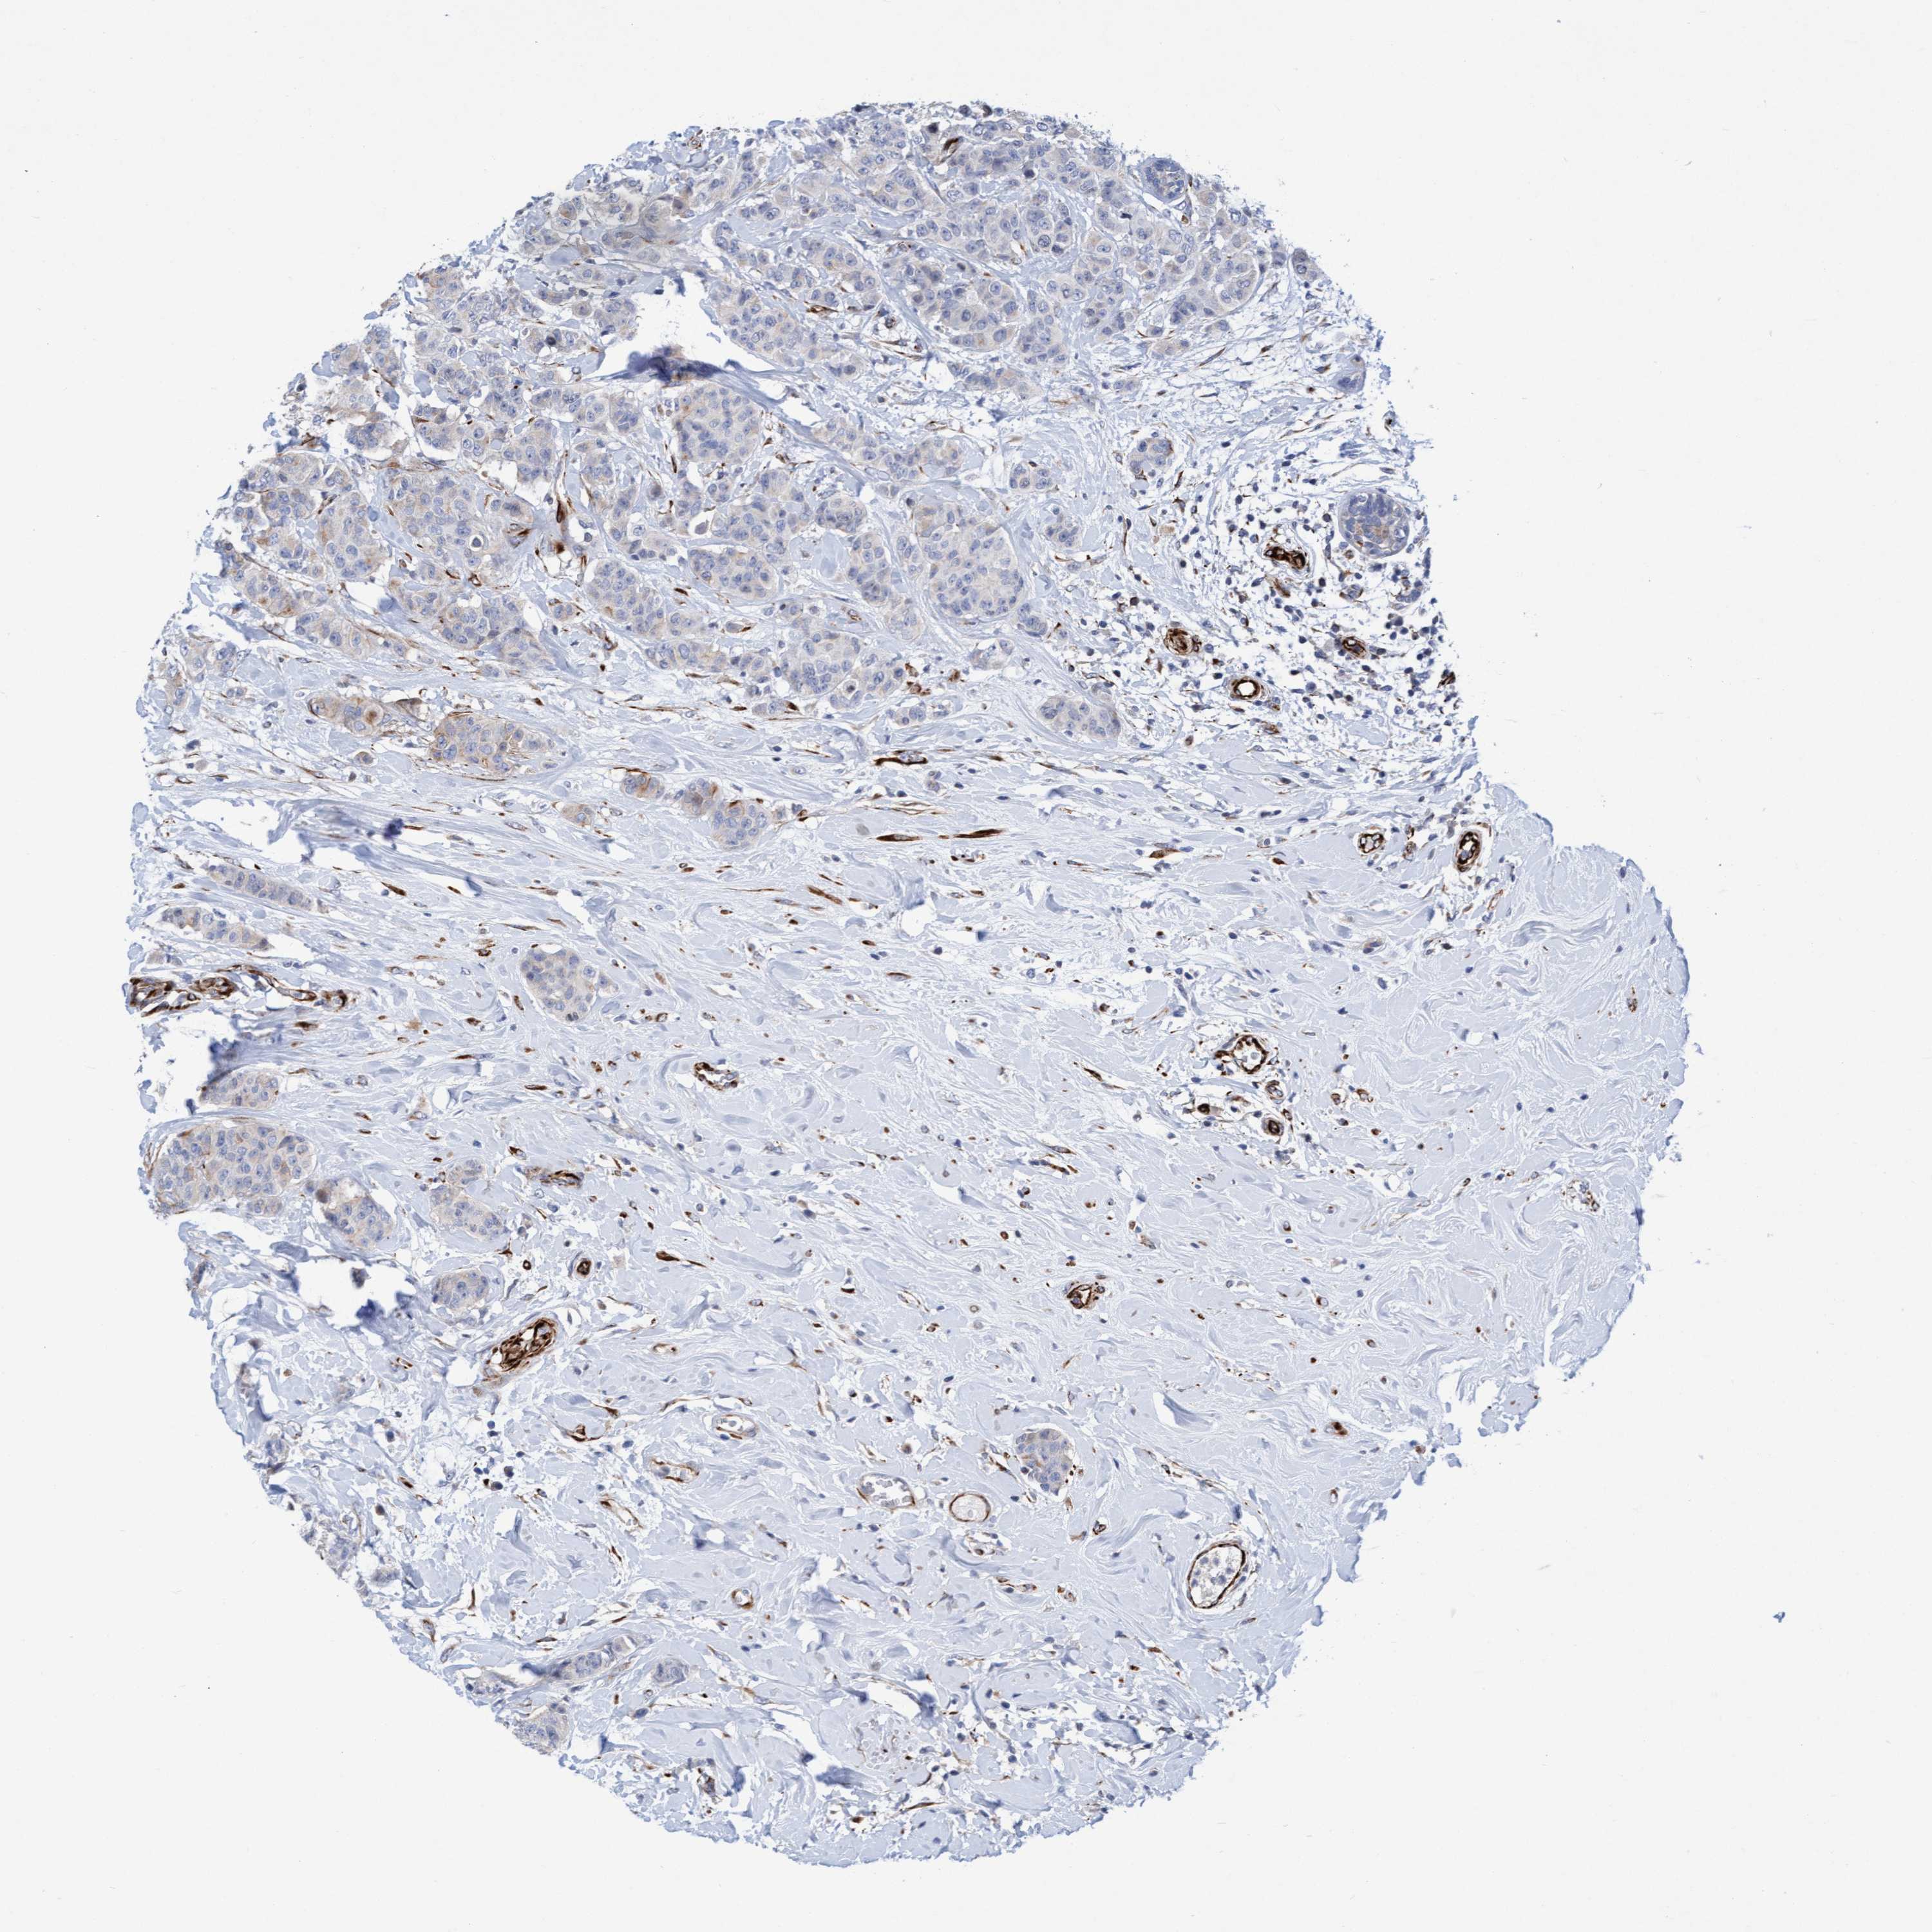

CANCER BREAST CANCER Show tissue menu

BRCA TCGA BRCA VALIDATION PROTEIN EXPRESSION